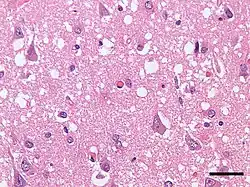

Micrograph showing spongiform degeneration (vacuoles that appear as holes in tissue sections) in the cerebral cortex of a patient who had died of Creutzfeldt–Jakob disease. H&E stain, scale bar = 30 microns (0.03 mm). | |

Prion diseases are marked by mental and physical deterioration that worsens over time.[5][6] A defining pathologic characteristic of prion diseases is the appearance of small vacuoles in various parts of the central nervous system that create a sponge-like appearance when brain tissue obtained at autopsy is examined under a microscope.[2][3] Other changes in affected regions include the buildup of PrPSc, gliosis, and the loss of neurons.[7]